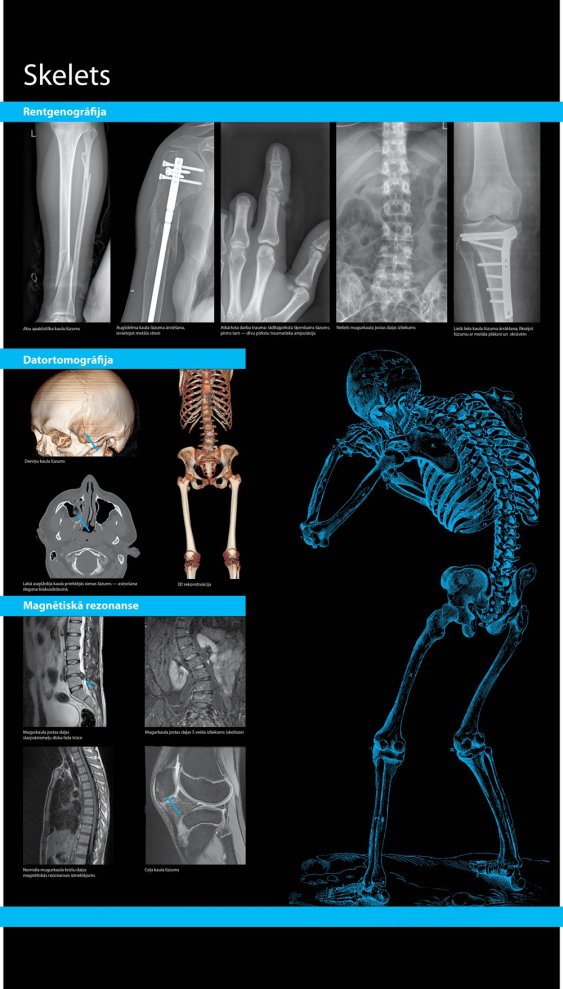

Izstāde iepazīstina ar medicīniskiem izmeklējumiem, kas slēpjas aiz sarežģītiem nosaukumiem — scintigrāfija, gamma kamera, radioloģiskiem izmeklējumiem — rentgenogrāfija, datortomogrāfija, osteodensitometrija, ultrasonogrāfija, magnētiskā rezonanse un radionukleīdā diagnostika. Izstādes planšetes bagātīgi ilustrētas ar attēliem. Atsevišķos plakātos apkopota informācija par smadzeņu, sirds asinsvadu, vēdera dobuma, reproduktīvo orgānu un skeleta izmeklēšanas metodēm.